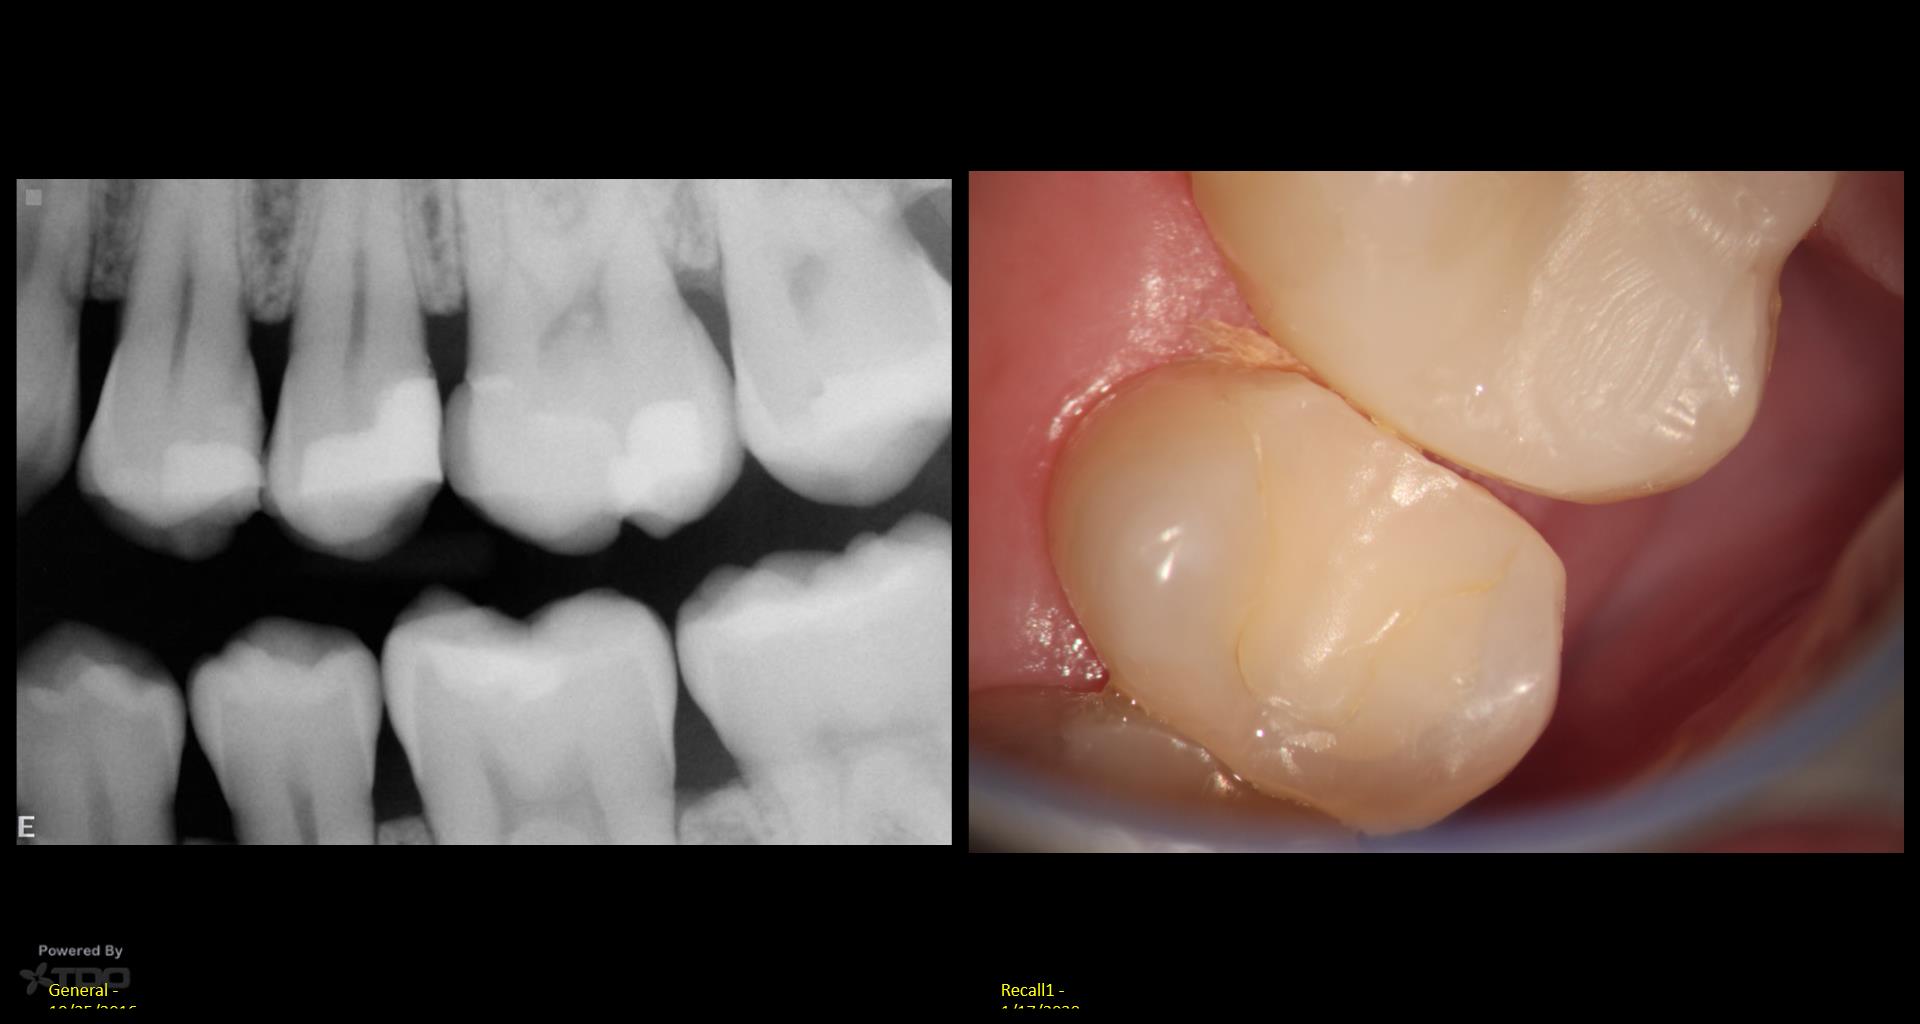

My hat is off to Dr. Ho and Dr. Dale who are doing this really well. Myself? Not too great….but I will get better….. There was caries under the DO on #13. So I tried a Clark Class 2, injected molded restoration. Took 2 hrs! I just can’t imagine doing this without a scope. Or for that matter, without an assistant’s scope. gbc